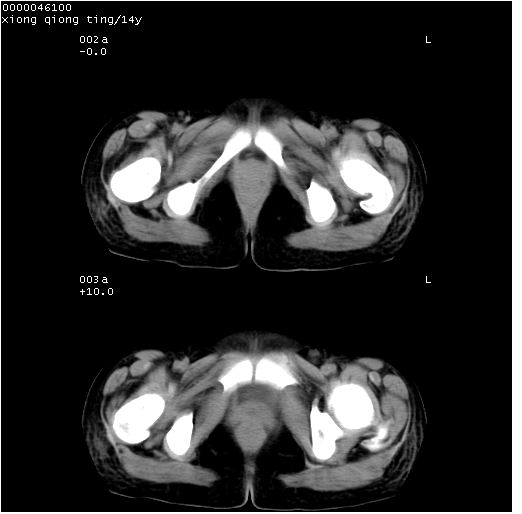

中下腹及盆腔ct轴位平扫+增强扫描(层厚10mm,螺距1.0,重建间隔10mm),图像如下:

(注:患儿检查当日上午9时口服胃肠道对比剂,下午3时许行ct扫描检查,未行对比剂直肠保留灌肠,检查当日患儿腹泻)

中下腹及盆腔ct轴位扫描(ps+ce)提示:腹部肠管明显充气扩张,并见数个不同宽度之气液平面;疑不全性肠梗阻或肠郁张。临床会诊考虑为患儿腹泻,肠郁张所致;后来未经特殊处理,患儿大便恢复正常,亦无腹胀。

临床出院诊断:1)结核性腹膜炎。2)腹膜后淋巴结结核。3)脂肪肝。